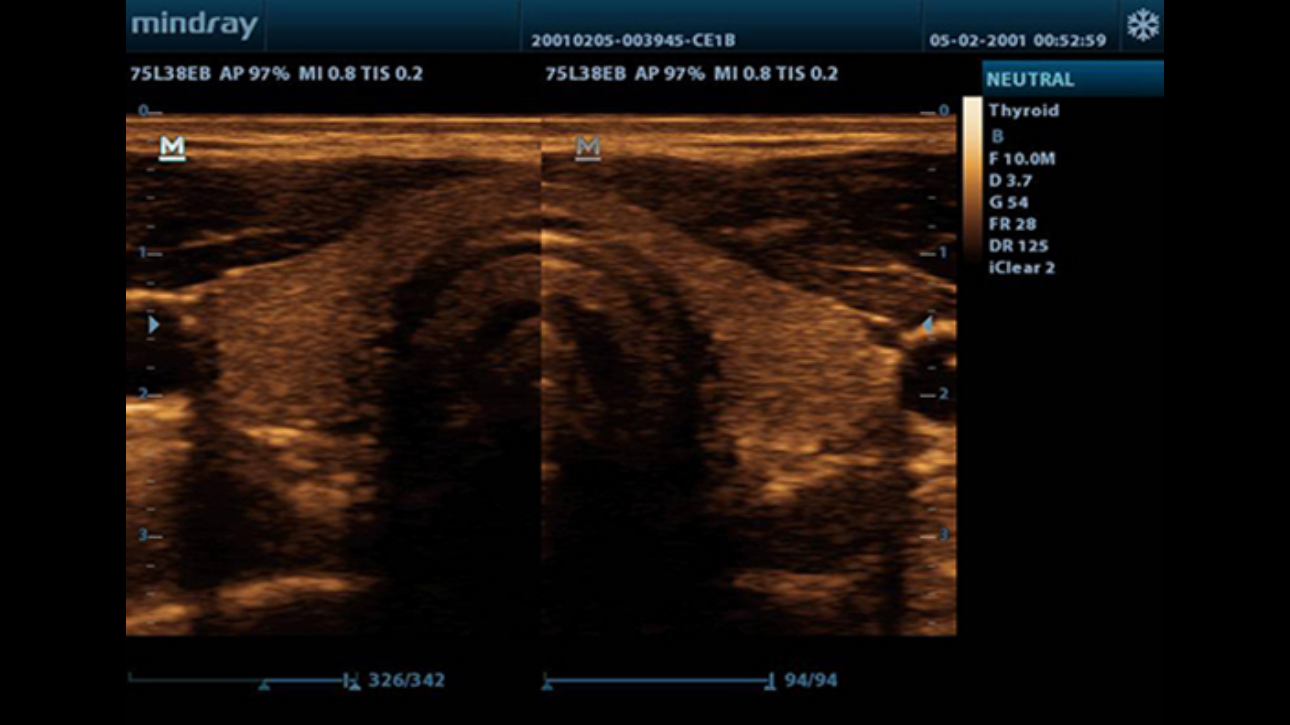

TSI

Tissue Specific Imaging optimizes the image quality based on the properties of the tissue being scanned. Four imaging options are available including general, muscle, fluid and fat.